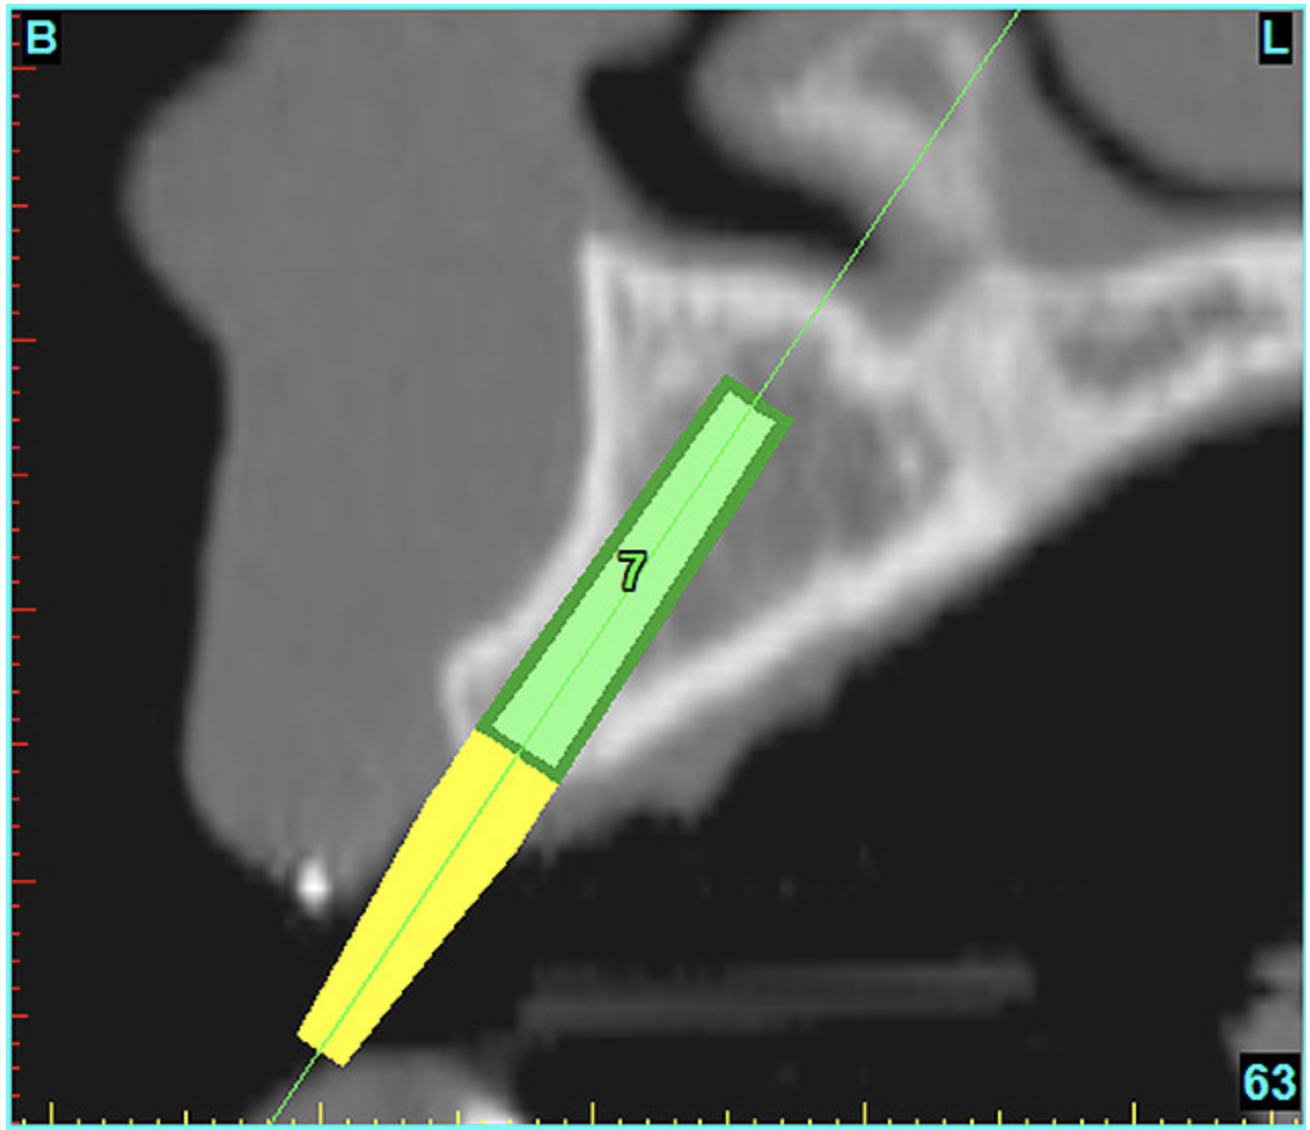

Using the interactive treatment-planning software application, the scan data was assimilated and both potential lateral incisor implant receptor sites were evaluated. It is a combination of the data and the methodology used to interpret the data that is the basis for defining a new paradigm in diagnosis and treatment planning. Proper evaluation of these images and correct use of the interactive treatment-planning software tools is essential in creating a decision tree of treatment options. First, the data from the scan was reformatted into panoramic, axial, and cross-sectional images. The undistorted cross-sectional images revealed the residual alveolar bone in the area of the right lateral incisor. Then, a simulated schematic implant was placed within the bone with an abutment extension to help visualize the connection to the restorative position of the tooth (Figure 4A). The Triangle of Bone® (TOB), a concept developed by the author to analyze bone quality, quantity, and disposition at prospective dental implant sites using CBCT scans, aided in determining available bone volume by defining a “zone” for proper implant placement18,19 (Figure 4B).

After reviewing the CT data and the decision tree, the bone within the “zone” of the TOB was evaluated and found to be satisfactory for implant placement. Because the goal of implant dentistry is not the implant but the tooth that is placed, true restorative-driven implant dentistry must begin with the assumption that the implant position should remain consistent with the tooth it is replacing, and the final implant-supported restoration.12,22-26 The TOB aids the clinician in understanding the link between the implant position and the desired restorative goal. The base of the geometric shaped “zone” is visualized by starting at the widest area of alveolar bone facially and superiorly. The apex of the triangle is positioned to bisect the alveolar crest (Figure 4B). The TOB, the overlay in the cross-sectional image, reveals whether adequate bone is available for implant placement. It also helps to identify concave facial bone defects, and accurately determine the width of bone at the crest. The author recommends using an interactive software application that provides the necessary measurement tools to accurately assess the bone anatomy.

Figure 4b  CT scan data was input into the treatment-planning software, which allowed (A) placement of a simulated implant and (B) the determination of the “zone” for proper placement.

Figure 4b